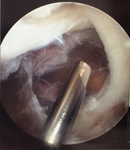

Arthroscopic resection of a popliteal cyst

From the collection of Dr John Kelly IV; used with permission

From the collection of Dr John D. Kelly IV; used with permission